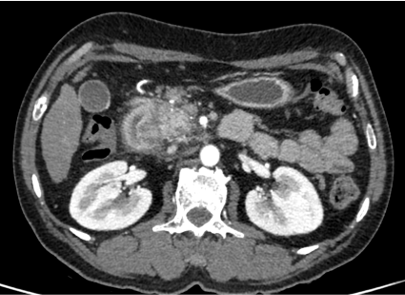

• Axial and coronal CECT images of the abdomen at the level of kidneys in venous phase.

• Left kidney appears hypo enhancing and shows perinephric fluid and fat stranding extending to the pararenal fascia. Mild ascites.